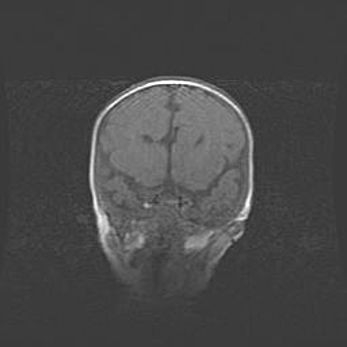

Церебральная ишемия II.

Возраст: 7 дней

Вес: 3350 г

Пол: женский

Окружность головы: 35 см

Срок гестации: 39 недель

Ишемия головного мозга – это состояние, которое развивается в ответ на кислородное голодание вследствие недостаточного мозгового кровообращения. У новорожденных она является следствием дефицита кислорода, что ведет к метаболическим расстройствам различной степени тяжести в тканях головного мозга, в том числе к развитию коагуляционных некрозов и гибели нейронов.